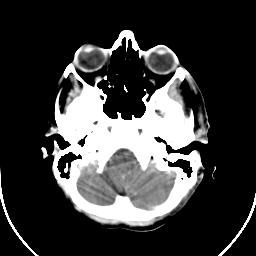

Metastatic bronchogenic carcinoma: Roentgen-ray CT (post-op) -- Slice #3

[Home][Help][Clinical] Slice 3